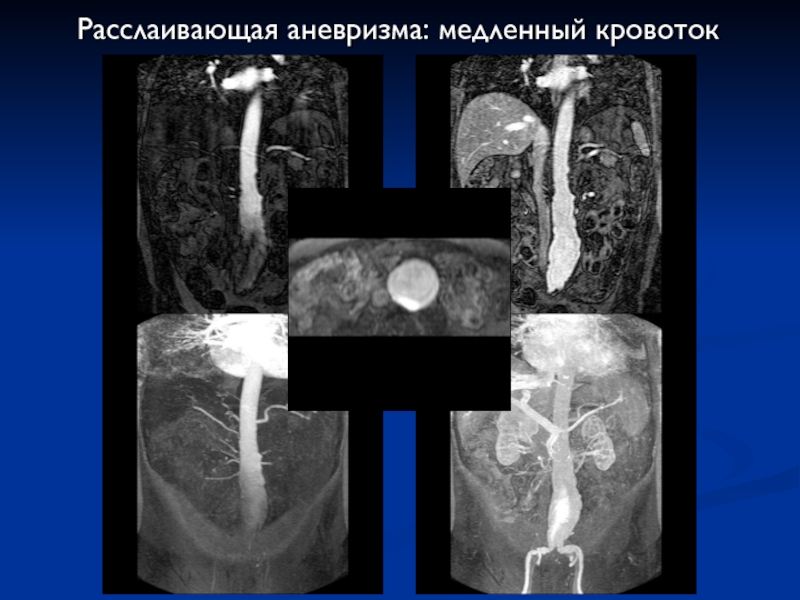

Слайд 49Расслаивающая аневризма: медленный кровоток

Расслаивающая аневризма: медленный кровоток